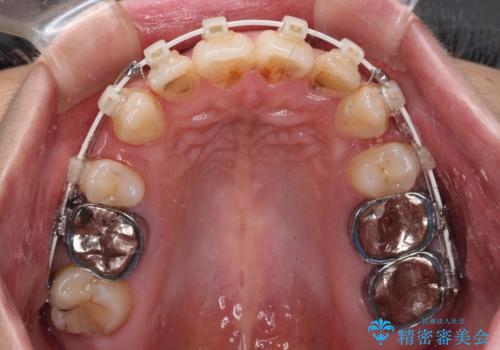

- 矯正装置

- 審美装置

上下ともに歯列が前方に突出していたため、上下左右の第一小臼歯4本を抜去し、ワイヤー装置による矯正治療を行うこととしました。